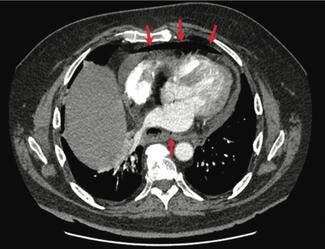

Fabrizio R. Assis, MD, and colleagues provide a review of ablation-related esophageal thermal injury (ETI), its risk factors, and esophageal protective strategies.